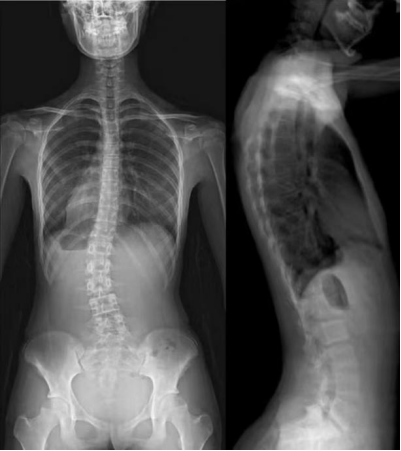

1.应用适应症:全脊柱摄影—青少年脊柱侧弯等畸形的矫正和人工腰椎椎间盘,可进行骨密度检查和负重全脊柱扫描。